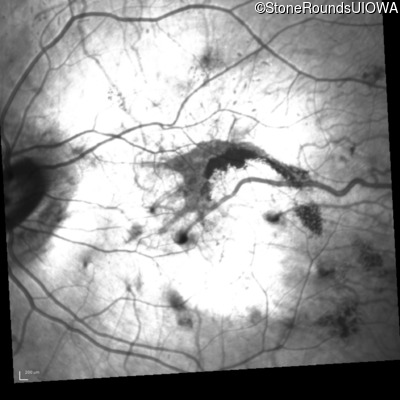

Infrared Fundus Photograph - Right - 5/350

Exemplar